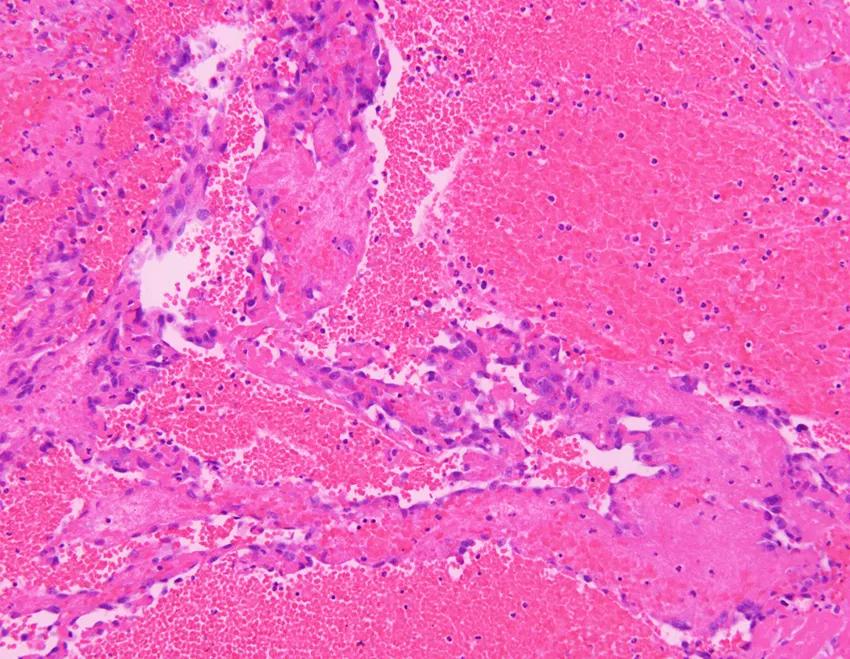

活检病理:

A 术中可见肺组织表现有弥漫性出血性病灶;B 低倍镜下病理病灶;C 高倍镜下可见大量梭形细胞;D 免疫组化可见CD34(+)、CD31(+)

术后病理:血管肉瘤

王岩主任(病理科)点评:

送检楔形切除肺组织一块,大体可以看到肺组织切面有凝血,并有大小不等的多枚结节。

镜下可以看到肺泡腔的弥漫出血,局部可以看到较多官腔样结构,衬覆上皮有异性性,另外可以看到成片的异性细胞在肺内多结节生长,呈梭形,可见到多量核分裂,这时候倾向为高度恶性肿瘤病变,镜下表现可排除上皮样血管内皮瘤,因为后者呈低度恶性、轻度异型性、核分裂相不如该患者明显。该患者组织学表现在病理上有以下考虑:肺腺癌?恶性间皮瘤?恶性黑色素瘤?血管肉瘤?硬化性肺细胞瘤?借助免疫组化结果CK(-)、TTF-1(-)Ki67(70%+)可以排除上皮样血管内皮瘤、肺腺癌、恶性间皮瘤、硬化性肺细胞瘤。HMB45(-)、melan- A(-)排除恶黑肺转移可能性。CD31(+)ERG(+)支持血管肉瘤的病理诊断。